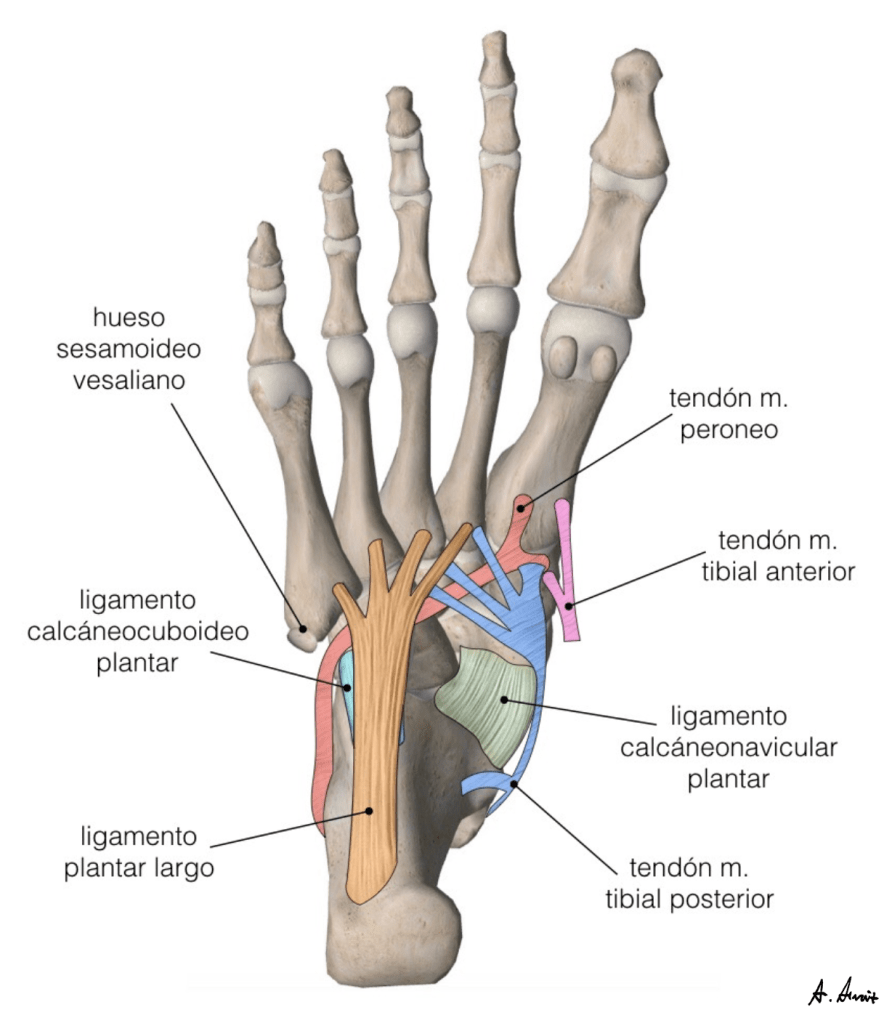

The following figures were made between 2014 and 2015. The simple shapes and bright colors reveal a somewhat naïve stage of drawing.